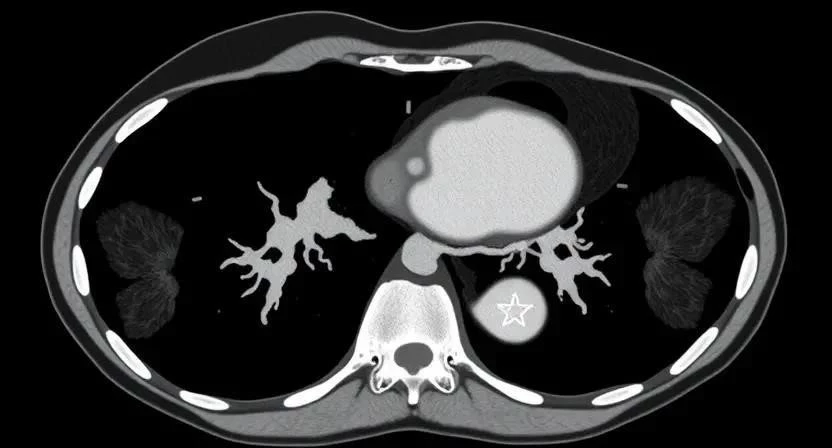

Компьютерная томография (КТ) в диагностике детского рака

Компьютерная томография (КТ) – это важный метод диагностики детского рака. КТ позволяет получить детальные изображения внутренних органов и тканей, что помогает выявить опухоли и оценить их размер и распространение. Подготовка к исследованию включает в себя ограничение приема пищи и, в некоторых случаях, введение контрастного вещества. Важно помнить, что КТ связана с воздействием ионизирующего излучения, поэтому ее следует проводить только по назначению врача и с соблюдением всех мер предосторожности. Я был свидетелем того, как КТ помогла врачам точно определить стадию заболевания у маленького пациента, что позволило выбрать наиболее эффективный план лечения.

Диагностика онкологических заболеваний у детей включает в себя различные методы: физический осмотр, анализы крови, визуализирующие исследования (КТ, МРТ, УЗИ) и биопсию. Этапы обследования могут включать сбор анамнеза, физический осмотр, проведение анализов крови и мочи, проведение визуализирующих исследований и, при необходимости, биопсию. Важность ранней диагностики трудно переоценить, ведь чем раньше будет выявлено заболевание, тем выше шансы на успешное лечение. Я знаю случаи, когда ранняя диагностика спасла жизнь ребенку.

| КТ | Получение детальных изображений внутренних органов | Высокая информативность | Воздействие ионизирующего излучения |